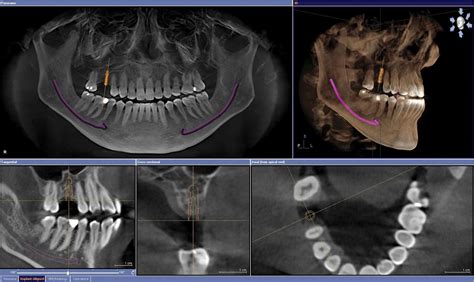

Un TAC dental, también conocido como Tomografía Axial Computarizada, es una técnica avanzada de imagenología que utiliza rayos X para obtener imágenes tridimensionales (3D) de los dientes, maxilares y estructuras circundantes. A diferencia de una ortopantomografía, la imagen es en 3D en vez de 2D, dando mayor información espacial, lo que nos da datos mucho más útiles a la hora de hacer un buen diagnóstico.

Gracias al TAC dental, tenemos una visión completa y precisa desde múltiples ángulos, permitiendo a los dentistas realizar estudios sobre la salud de los dientes, las encías y el hueso maxilar con la mayor exactitud posible. Esta exploración permite realizar tratamientos complejos, como la colocación de implantes dentales, la extracción de dientes impactados y la evaluación de patologías maxilofaciales.

El TAC dental ofrece una gran serie de beneficios que lo convierten en una herramienta indispensable en la odontología moderna. Su principal diferencia respecto a las radiografías convencionales es su capacidad para obtener imágenes en 3D, lo que permite contar con una visión más completa y detallada de la anatomía dental y ósea de una persona.

- Colocación de implantes: El TAC es imprescindible antes de la colocación de implantes dentales, usándose durante la fase de estudio para observar y analizar las estructuras óseas del paciente.

- Regeneración de hueso: Permite observar la estructura ósea del paciente y valorar si dispone de suficiente cantidad de hueso para colocar un implante.

TAC dental en implantología

El CBCT permite identificar la mejor vía para el acceso quirúrgico, reduciendo el riesgo de lesiones neurológicas y dentales. El TAC dental nos da la opción de colocar “virtualmente” los implantes gracias a los diferentes software que existen. Esto asegura que a la hora de la intervención el cirujano sepa con seguridad cuál es lugar más apropiado, facilitando que en intervenciones más complejas la tasa de éxito aumente.